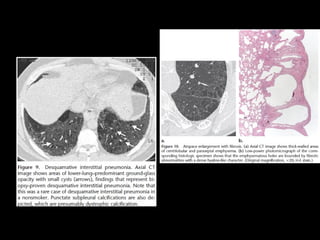

DIP

• “alveolar macrophage pneumonia”

• Vidrio esmerilado

• LI y subpleural

• Quistes aéreos, panalziación poco frecuente

• DD: RB. NSIP: ausencia de fibrosis, bq x

tracción

• LBA: macrófagos

RB-ILD

• RB Asintomático, hallazgo

• Representan un continuo por la injuria del

tabaquismo

• Overlap

• RB ILD se asocia más a fumadores

• DIP: incluye drogas, polvo

CT

• Nódulos centrolobulares LS

• Atrapamiento aéreo

• Engrosamiento septal interlobular

• DD: neumonitis por hipersensibilidad

subaguda, DIP y NSIP

• Biopsia: bronbquiolitis acumulación intraluminal de

macrófagos pigmentados